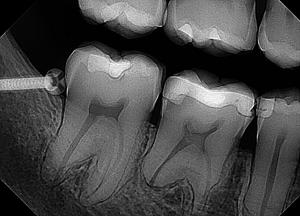

An example of a good X-ray image